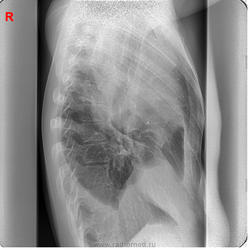

Мужчина 28 лет. Болен около месяца. В первую неделю заболевания была лихорадка. Практически не лечился. Всё время работал.

Беспокоит сильный кашель, 2 недели назад с гнойно-кровянистой мокротой, последние дни кашель до рвоты, из-за которого почти не ест и может спать только на правом боку, мокрота скудная, светлая. Похудел, слабость, одышка при небольшой нагрузке.

Сегодня решил проверить своё здоровье на флюорографии. Предыдущая флюорография 6 лет назад.

центральный рак, ателектаз верх. доли

На мой взгляд, центральный рак + параканкрозная пневмония + базальный параканкрозный плеврит.

"может спать только на правом боку"-патогномоничный признак полости(-ей). предположу: была пневмония (лихорадка),к-ая абсцедировалась (не лечился).абсцесс прорвался (мокрота,кашель до рвоты), содержимым обтурировался в\д бронх,вследствие чего возникла гиповентиляция верхней доли. Ну и экссудативный плеврит в довесок

Я рассуждал почти также. Только настоящего ателектаза, пожалуй, нет. Написал: "Абсцедирующая пневмония без дренирования абсцесса в настоящее время, с ателектатическим компонентом. Экссудативный плеврит есть и свободный и осумкованный. Линейку сделать можно, но надо сперва пролечить, получить динамику. Для начала в прорыв брошена кавалерия…, ну терапевты, значит.

Поддержу недренированный абсцесс/абсцедирующую пневмонию. Ну, и гидроторакс, конечно.

Интересное наблюдение. Поддерживаю 3 последних поста. ИМХО:скиологически, корректно  вести речь, о выраженном выпоте в плевральной полости с осумкованием, частичном  компрессионном ателектазе верхней доли.Субстратом пневмонии, по видимому является округлый инфильтрат в прикорневом отделе ( абсцесс который конечно, недренировался, т.к. в случае дренирования был бы виден уровень жидкости) и  перибронхиальная инфильтрация в нижнем поле.

При недренированном абсцессе такого размера у молодого человека была бы лихорадка под 40 и не только в первую неделю заболевания. Как вариант предлагаю рассмотреть саркому правого лёгкого.